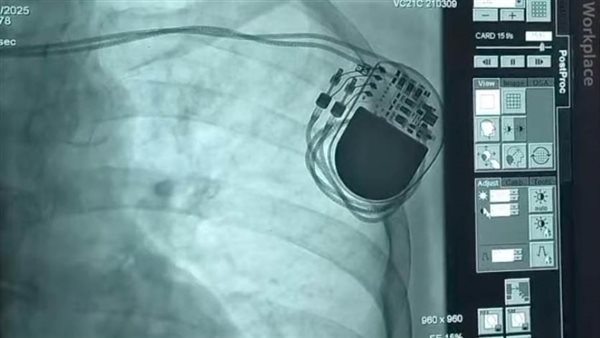

إنقاذ حياة مريضة مسنة بتركيب منظم ضربات قلب دائم داخل قسم قسطرة القلب بمستشفى شرق المدينة التخصصي

طبقا لتوجيهات "ا.د.مها ابراهيم" رئيس أمانة المراكز الطبية المتخصصة التركيز على تقديم خدمات طبية طارئة و متميزة لجميع المرضى، ومتابعة وإشراف "د.ميرفت السيد" مدير المركز الافريقى لخدمات صحة المرأة والمشرف العام على مستشفيات أمانة المراكز الطبية المتخصصة بالإسكندرية، تم إعلان نجاح الفريق الطبي بوحدة قسطرة القلب بمستشفى شرق المدينة برئاسة "د.عبد الله الفرماوي" مدير المستشفى، في إنقاذ حياة مسنه تبلغ من العمر 70 عاما وتركيب منظم ضربات قلب دائم ثنائي حيث حضرت المريضة إلى قسم الطوارئ تعاني من ضعف في كهربية القلب و تباطؤ ضربات القلب، وهي حالة خطيرة أدت إلى بطء شديد في ضربات القلب و اغماءات متكررة وفقد اتزان وتباطؤ ضربات القلب الى 30 في الدقيقة، وكانت المريضة قد دخل قسم الطوارئ بالمستشفى وهي في حالة حرجة شديدة وإعياء تام وعلى الفور تم استدعاء الاستشاريين بوحدة قسطرة القلب وتم عمل تخطيط للقلب وموجات فوق صوتية وتم تشخيص الحالة ودخولها لغرفة عمليات القسطرة فورا، وأجريت لها عملية تركيب المنظم الدائم بنجاح داخل وحدة القسطرة بالمستشفى، وخرجت من العناية المركزة بحالة مستقرة وتحسن ملحوظ.

وأوضحت أيضا، أن جهاز منظم ضربات القلب ومزيل الرجفان هو جهاز صغير الحجم يُزرع في منطقة الصدر للمساعدة على التحكم في نبضات القلب. فيتتبع معدل ضربات القلب، وفي حالة اكتشاف إيقاع غير طبيعي في القلب يعمل على توصيل صدمة كهربائية لاستعادة نبضات القلب الطبيعية ويُستخدم لمنع القلب من النبض ببطء شديد. و يتطلب زرع جهاز تنظيم ضربات القلب في الصدر إجراءً جراحيًا.